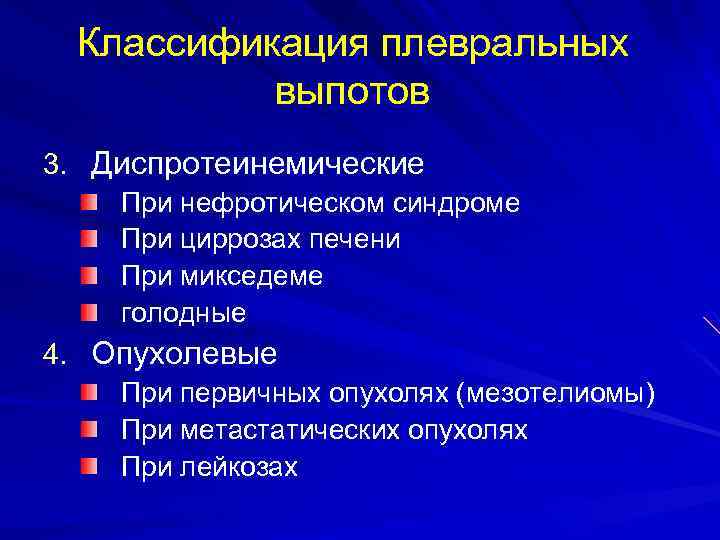

Диагностика плеврального выпота: что нужно знать